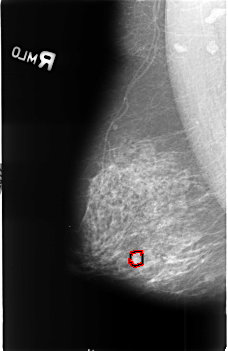

FILE: B_3406_1.RIGHT_MLO.OVERLAY

TOTAL_ABNORMALITIES 1

ABNORMALITY 1

LESION_TYPE CALCIFICATION TYPE PLEOMORPHIC DISTRIBUTION CLUSTERED

ASSESSMENT 4

SUBTLETY 3

PATHOLOGY MALIGNANT

TOTAL_OUTLINES 1

BOUNDARY